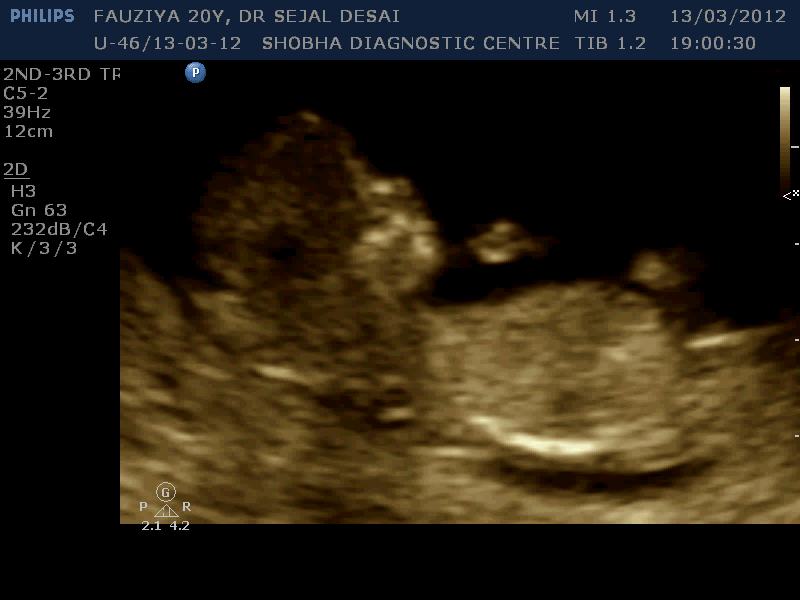

Routine Sonography

To know growth and general condition of the baby.